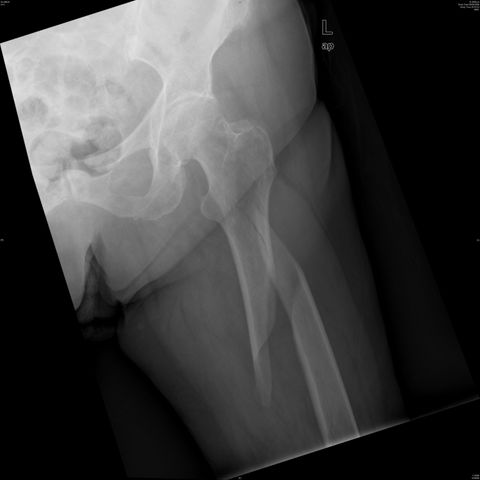

Fractura de cuello de fémur.

Fractura de cuello de fémur

Fractura de cuello de fémur con tornillos de tracción